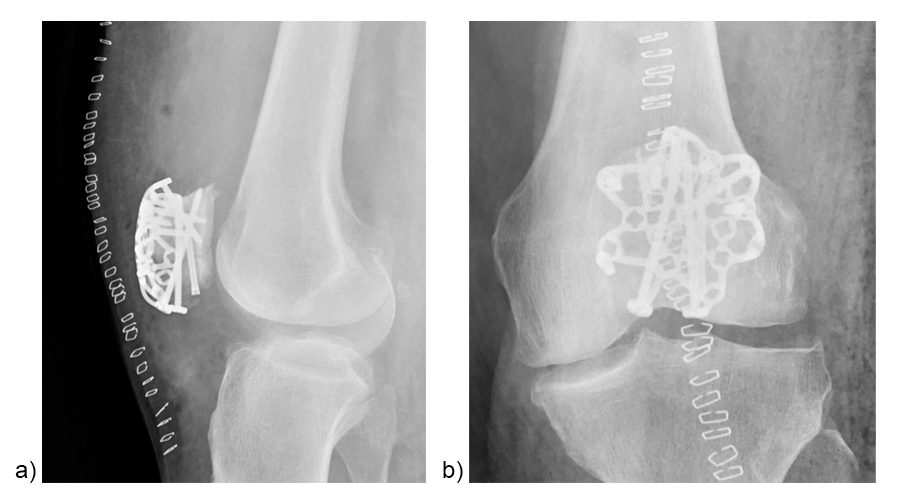

A 73-year-old woman sustained a right 34-C3.1 patella fracture during a hiking injury (Fig 1). X-ray analysis revealed that the distal pole was fractured in four fragments (Fig 2). After fracture reduction, a three-hole plate was used with three inferior to superior locking screws in the coronal plane through the holes of the plate legs and five anterior to posterior locking screws (Fig 3 and Fig 4).

A standard three-hole patella plate was chosen and bent according to the template. A central trans-patellar tendon stab incision was made to insert the middle plate leg when positioning the plate (Fig 10). The plate was provisionally fixed to the proximal patella fragment. The inferior to superior pole screw was inserted first as the 'primary' screw through the preselected plate hole of the middle plate leg to prevent collision with subsequent 'secondary' anteroposterior screws. Bicortical pole screw placement increases the stability of the construct. In this plate configuration the plate was used as a “basket plate” to stabilize the fracture. A second pole screw was inserted through the lateral plate leg.

The plate fixation was finalized by placing the monocortical AP locking screws. Subsequently, the sutures were tightened to the patellar tendon and the extensor mechanism (Fig 11). The plate may help to enhance the suture fixation.

Figure 12 illustrates the final fixation construct. The patient was allowed to perform early active knee movement at 2 weeks.